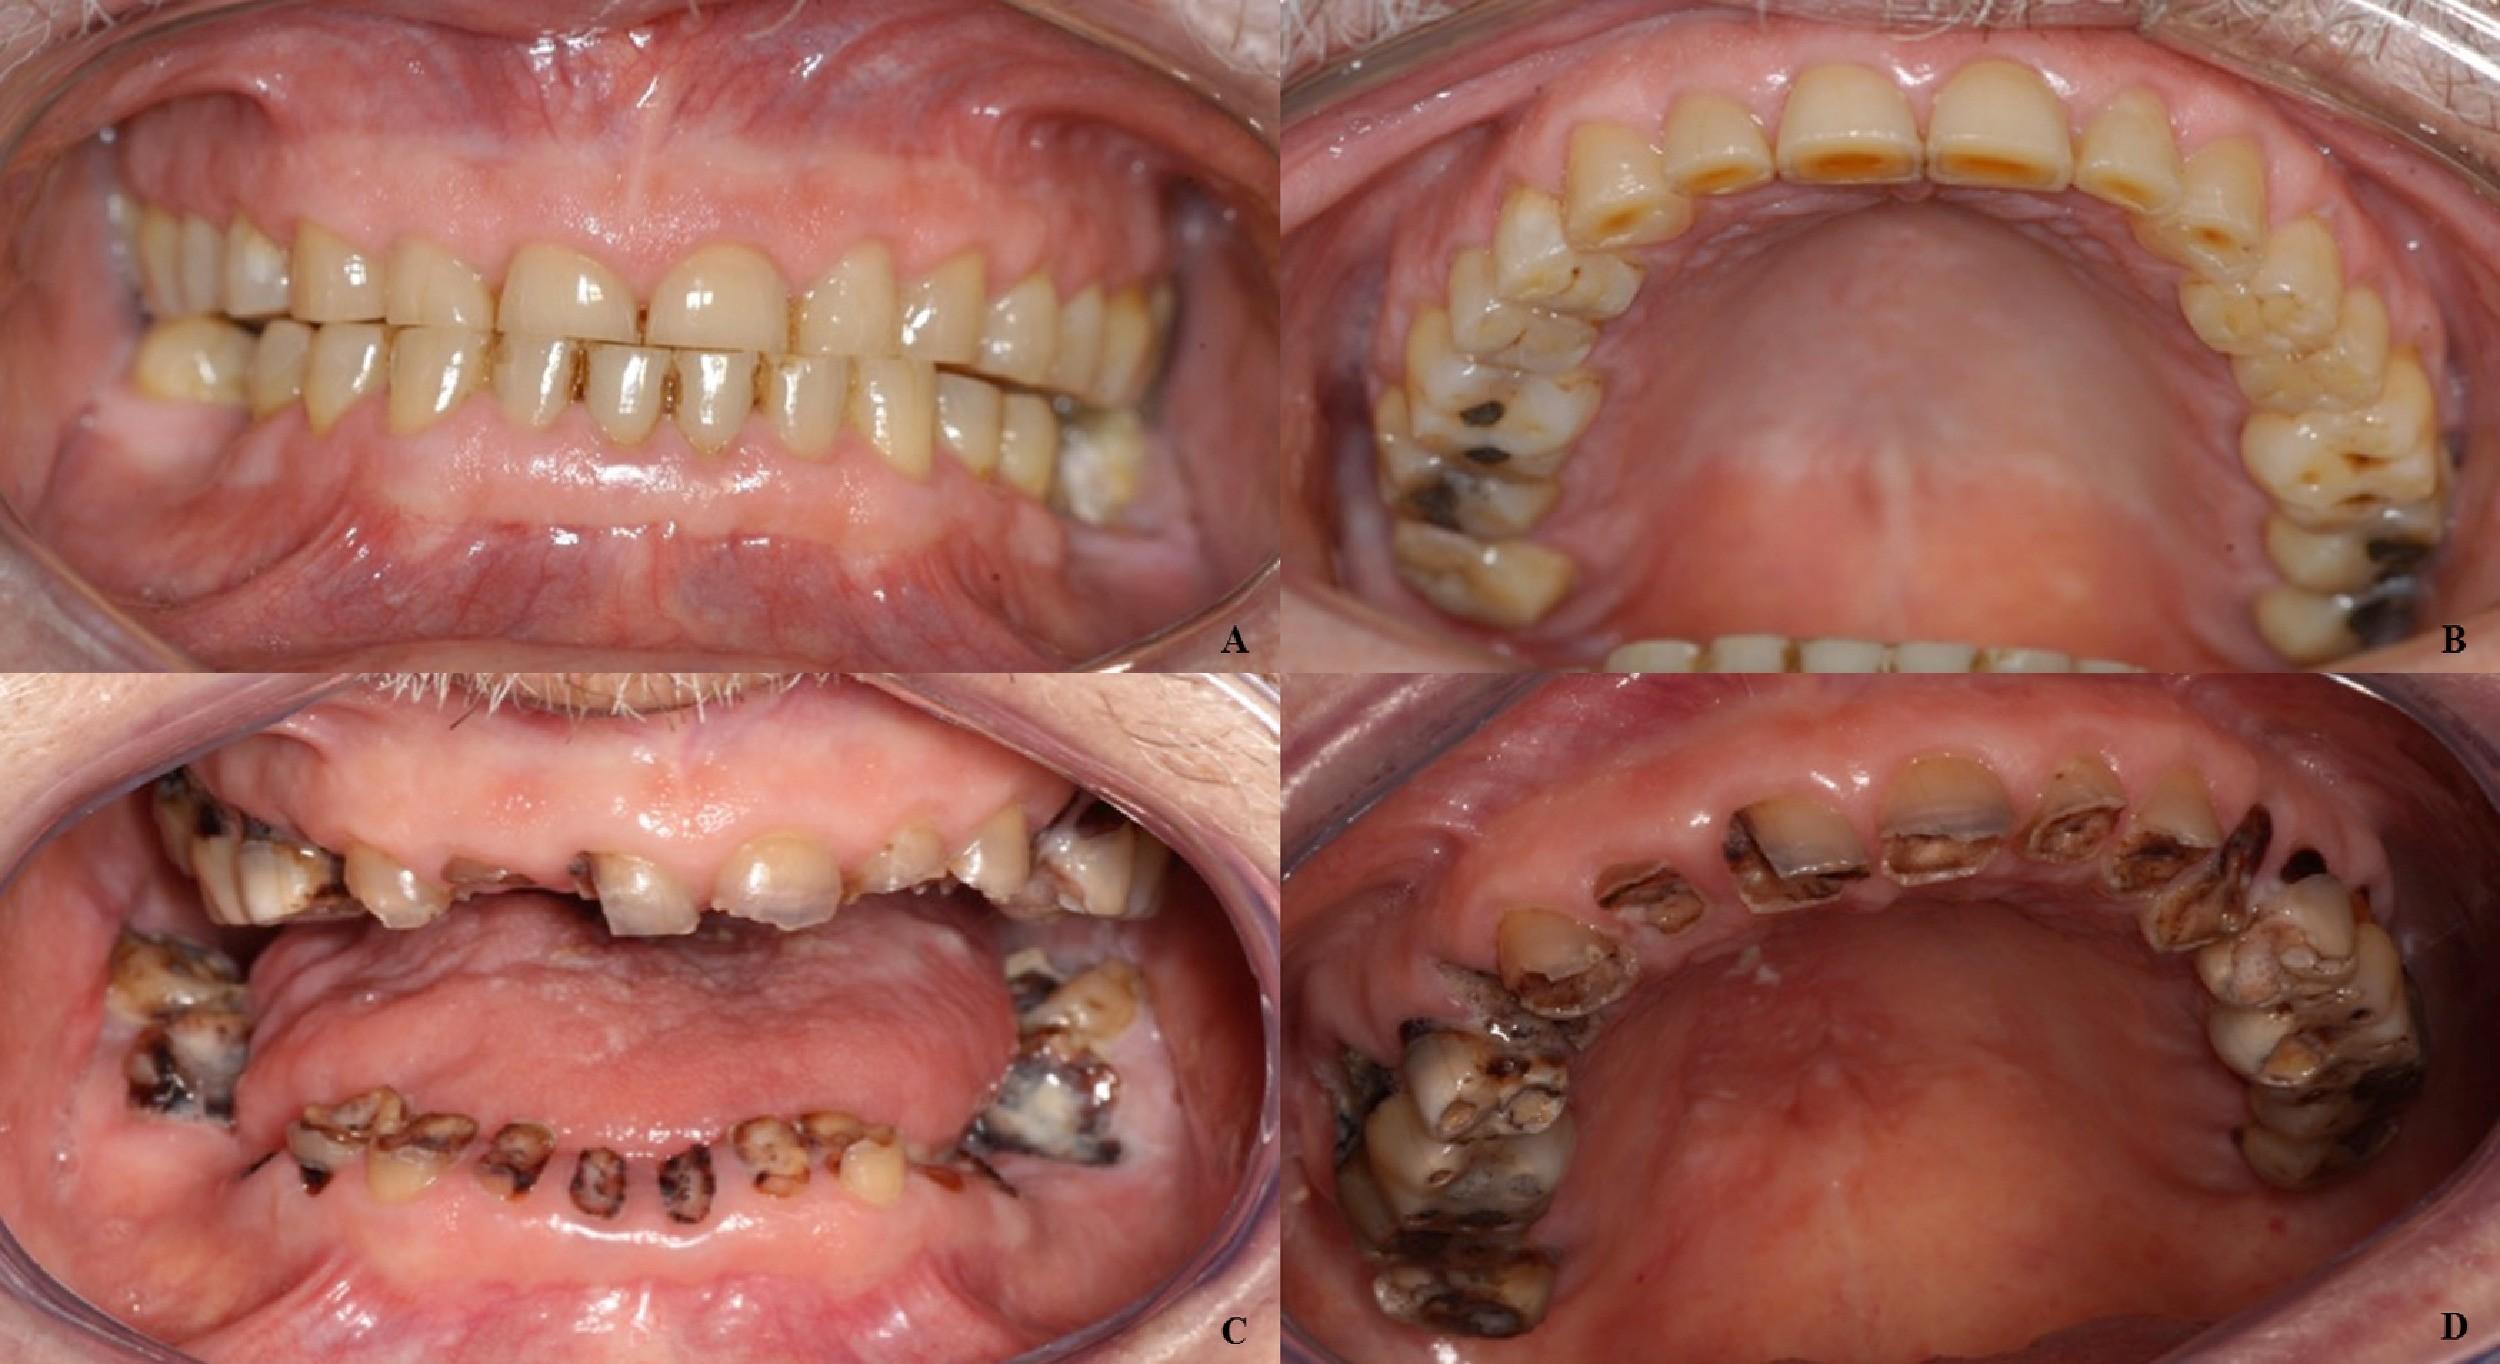

Beyond Myeloma Therapy: Oral Health Survivorship

Katharine (Kate) Ciarrocca, DMD, MSEd

Director, Oral Medicine, Duke University Hospital

Common Complications of Cancer Therapy

Why is the mouth so susceptible?

Oral Evaluation Before Cancer Treatment

Oral Health During Cancer Treatment

Treatment Related Oral Complications

Due to both direct damage to oral tissues secondary to cancer treatment and indirect damage due to regional or systemic toxicity